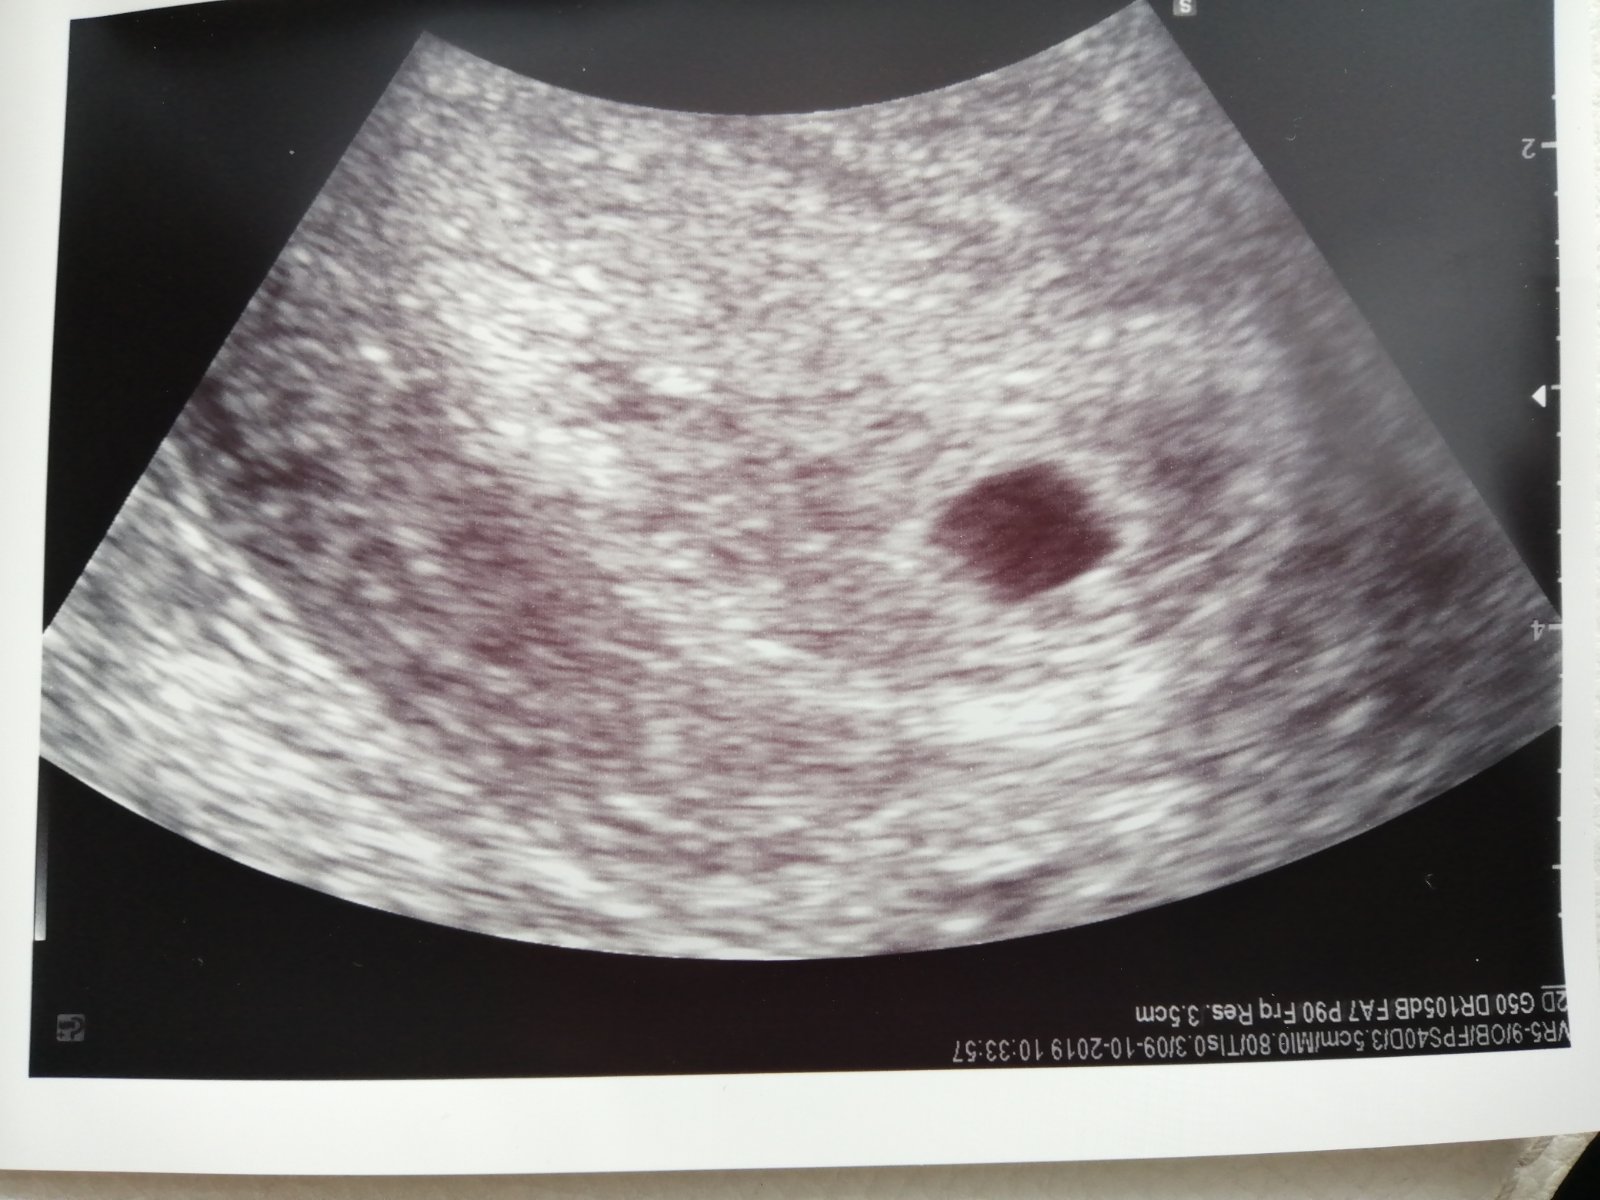

ahojky holky vcera jsem byla na kontrole a doktor mi rekl ze vidi tehotenstvi ale ze mam prijit 31.10.2019 vzal mi krev aby jsme videli ze krasne bije srdicko a abych dostala fotecku takze budu cekat strasne dlouha doba

@zizibou děkuji moc ani jsem necekala ze takhle brzo bude videt.. Příště budu uz kolem 9 týdne to uz bude jiná podívaná.. Tesim se jako malé dítě na Vanoce.. A ty de neboj! Vse dobře dopadne!

Ahojky holky jsem 5tt+4 myslite ze doktor uz neco uvidi na ultrazvuku 4tt+4 mi bral krev presne pred tydnem rikal mi ze je zvetsena sliznice testy mam vsechny pozitivni mohl by uz neco videt mam 14 dni vynechanou menses.

@julinecka24 ja byla přesně v 5+4 taky a byla dutinka a malá smouha.. Někdy není vidět ještě nic, je brzo.. Ale každá jsme jina..

@julinecka24 když jsem byla v minulém těhu brzy na utz, přibližně stejně, jak píšeš, byl vidět gestační váček a ten žloutkový vak. Teď nevím, zda to říkám správně 🙈😅. Už je to nějaký ten pátek 😁. Ale prostě vidět tam toho bylo celkem dost 😉

@julinecka24 ahoj ja měla vidět že se vajíčko dobře usadilo.. Pak jsem sla za 14 dni a byla fazolka přeji hodně štěstí